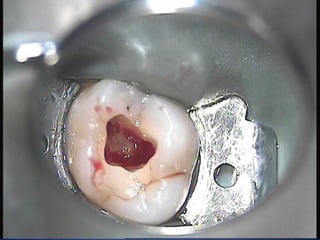

CAMARA PULPAR

•Se aloja la pulpa cameral constituido por paredes: Oclusal o incisal o techo, cervical o piso (dientes multirradiculares) paredes mesial, distal, vestibular y lingual.

PISO PULPAR

Se presenta como una superficie convexa lisa y pulida; en la parte media donde la porción es mas alta recibe el nombre de ROSTRUM CANALIUM; a nivel de sus ángulos presenta unas depresiones denominadas vaguadas que desembocan en las entradas de los conductos